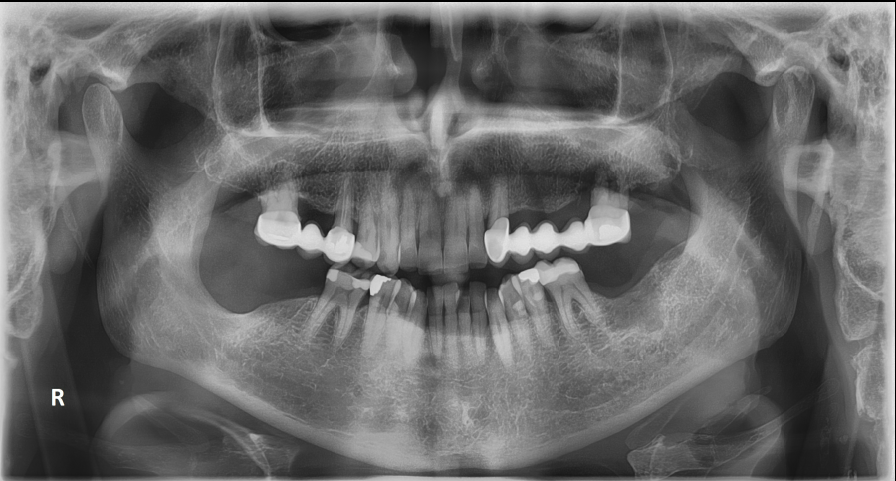

Άνδρας ασθενής 77 ετών εμφάνισε προ 4 ετών ενδοστοματικό ογκίδιο για την ακτινολογική διερεύνηση του οποίου συστήθηκε η πραγματοποίηση πανοραμικής ακτινογραφίας. Στην πανοραμική ακτινογραφία παρατηρήθηκε η παρουσία ευμεγέθους ακτινοδιαυγαστικής αλλοίωσης η οποία απεικονίζεται στην περιοχή της αναφερόμενης ενδοστοματικής βλάβης.

Πανοραμική Ακτινογραφία 12/2020